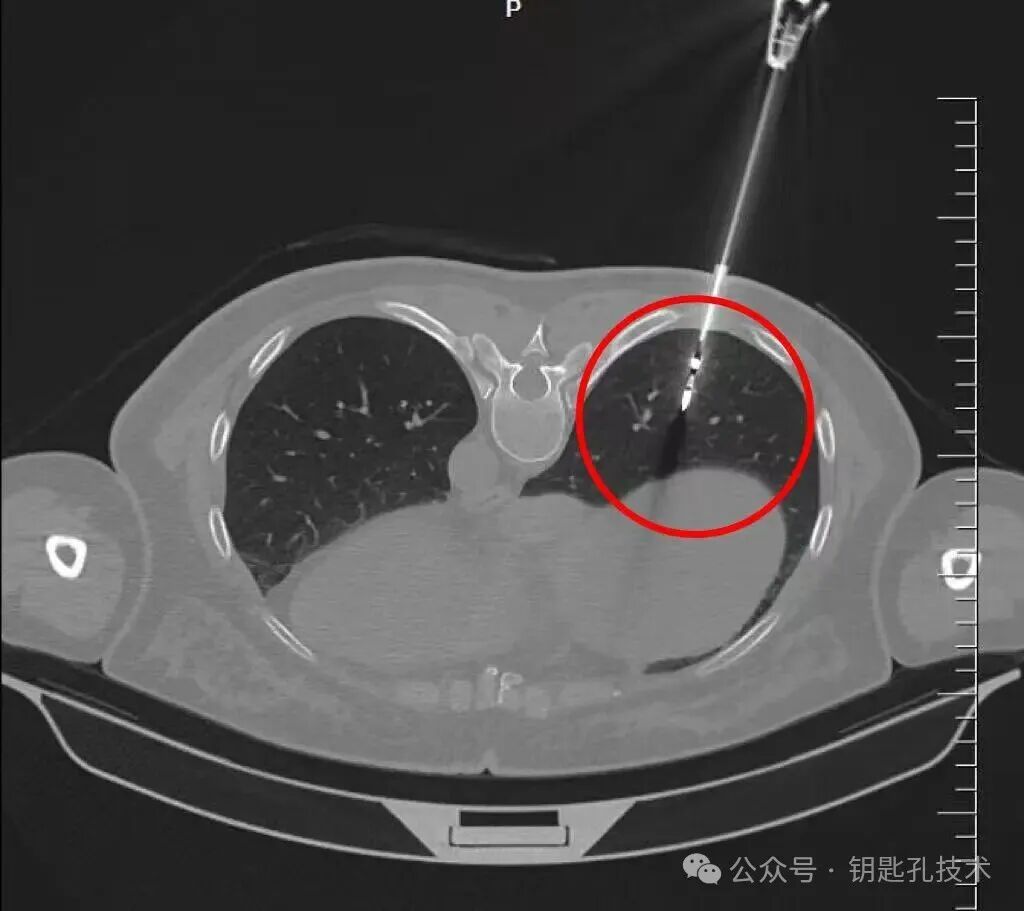

图1:患者查体发现右肺下叶一磨玻璃结节,密度偏高,CTR占比高,并见血管穿行其中,抗炎治疗后结节未见明显变化,符合高危结节表现

图2:消融针精准到达预定位置,术后消融范围完全覆盖结节并4阴性区域